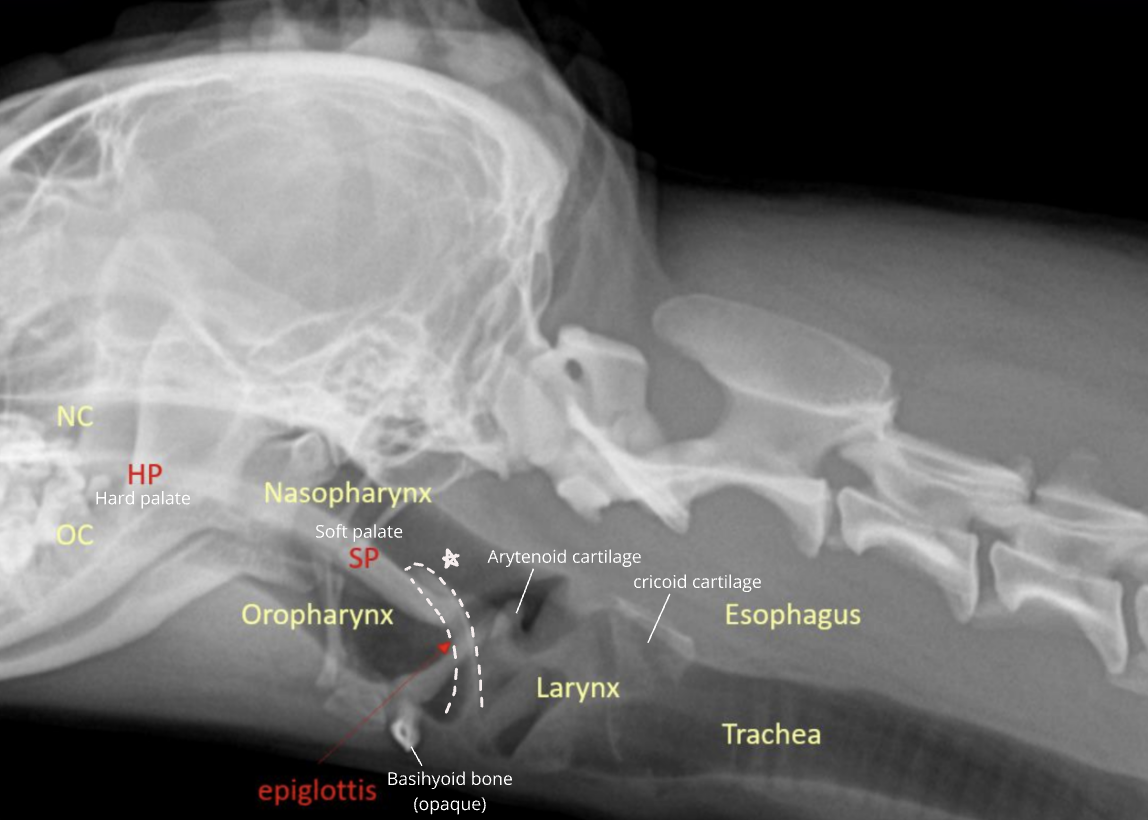

| Upper respiratory system |

|---|

![]() |